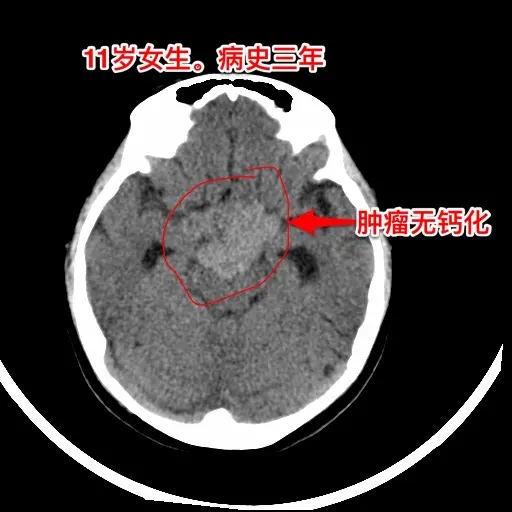

生殖细胞瘤对化疗很敏感,降低颅压才安全。之前我发的11岁四川女孩子,因多饮多尿、视力下降、多睡等症状在我科住院。住院后经用药物治疗,精神状态明显好转。 我们怀疑肿瘤为生殖细胞瘤,因肿瘤体积巨大,综合考虑病史、体检、手术风险、对化疗、放疗的敏感性,我们于8月13日给患儿作了肿瘤活检手术。 手术后病理报告为纯生殖细胞瘤,未见其他肿瘤成分(当然活检取得的标本很少,这个结论不是百分百的可靠) 8月20日开始化疗,8月21日患儿出现精神差、多睡症状,和住院前的症状相似。复查CT显示肿瘤在活检手术后继续增大,而且造成了脑积水,颅压高,见图2。此时不得不为患儿作急诊脑室外引流手术,以求降低颅压,为化疗保驾护航。随后继续化疗。 化疗的第三天,CT显示肿瘤体积有所缩小,见图4。 化疗一周后,肿瘤体积显著变小了,脑积水明显减轻了,见图5。病人的精神状态好转。拔除了脑室引流管。 希望化疗能将肿瘤完全杀灭,再结合放疗,将肿瘤完全治愈。